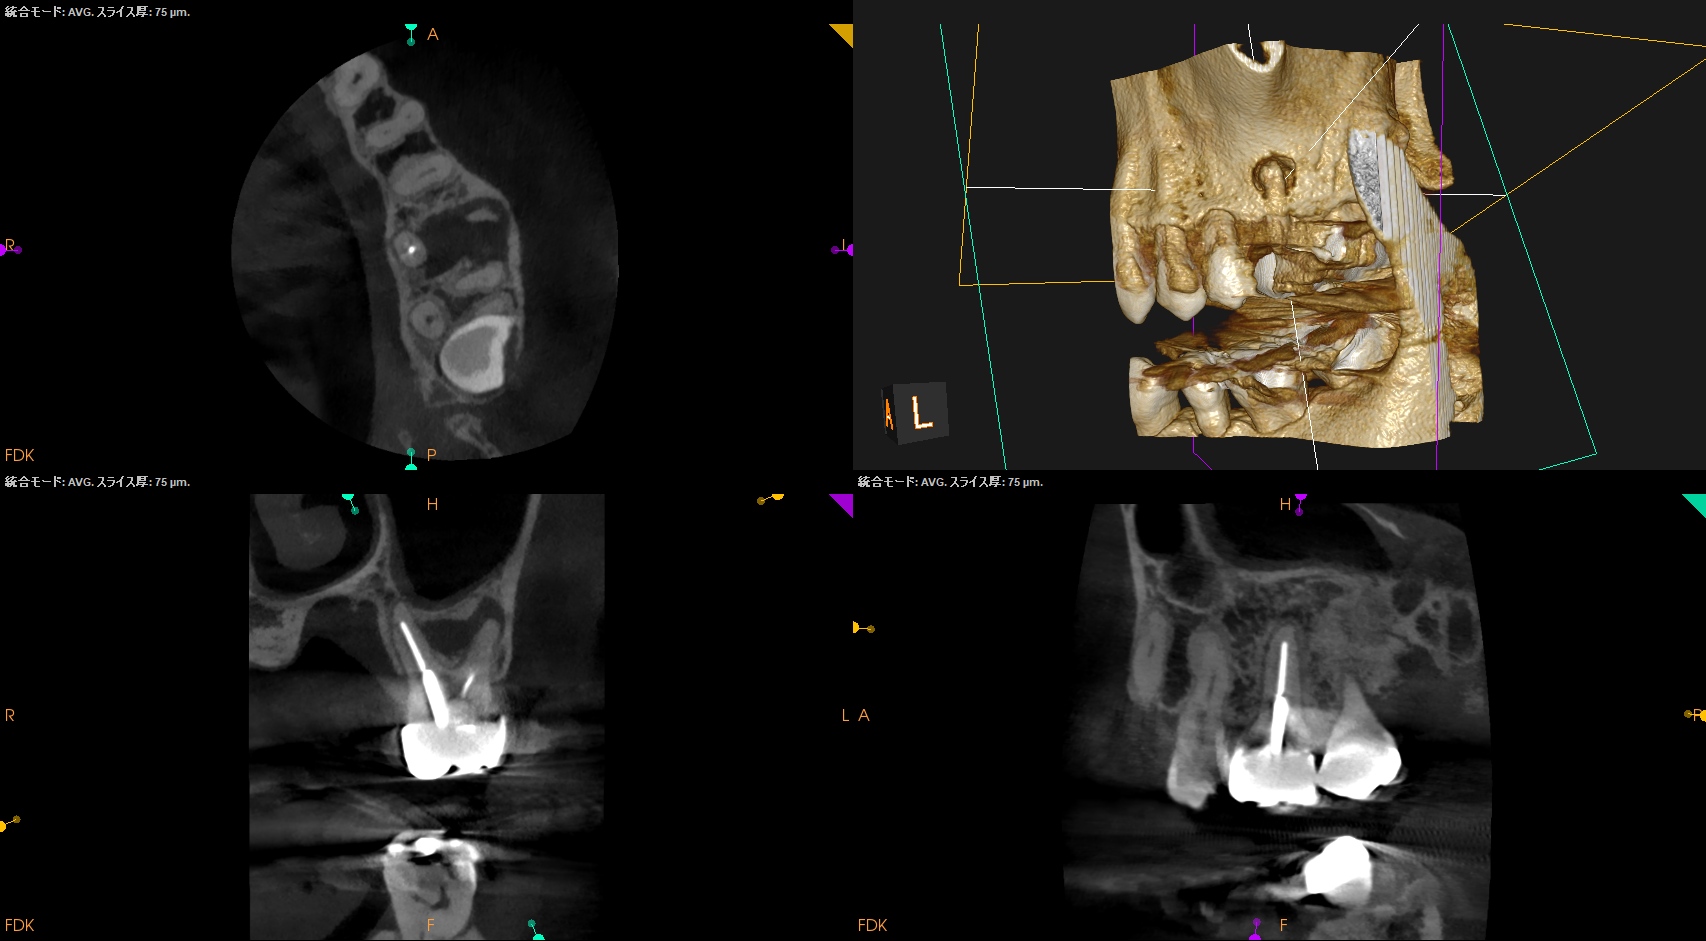

MB2を発見・穿通させる必要があるかどうか?はこのように術前にCBCTを正しく分析すれば予想ができる。

MBは、

MBの作業長の予測は18~19mm(臨床的にはここからクラウンの厚み, この際はMB部分を引く必要性)ということがわかる。

DBは、

DBの作業長予測は17.4mm(ここからDBのクラウンの厚みを引いた長さ)

になろう。

そのためのガイドマップにCBCTは必須と言える。